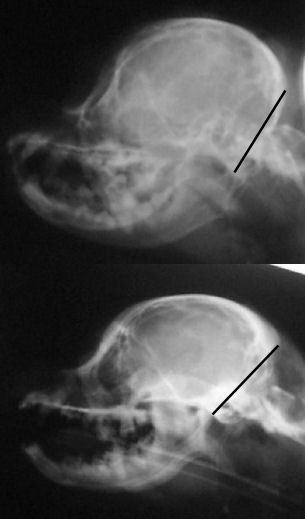

Based on my findings, a study was eventually done to determine

if a skull x-ray could be used to determine amount of CM. The

more CM, the more likely there is to be SM--in most cases. This

study did show there was one skull measurement that did indicate

amount of CM. Here is a comparison of two skull x-rays which

show why this particular measurement indicates amount of CM. The

top one is a skull x-ray of a Cavalier with severe CM (and has

SM as well) and the bottom one is a skull x-ray of a Cavalier

with very little to no CM (and no SM).

The line was drawn from right in front of the 'hole'

(black spot), center of that curved bone (the 'jaw hinge' area)

to where the most thickened area of the skull ends (and the

occipital area begins). In the dog with almost no CM and no SM

you can CLEARLY see there is a lot more lower backskull left

behind/below that line as compared to the dog above--which

literally has almost none! This also happens to be the area

where the cerebellum sits so it would be common sense that the

dog in the top x-ray would have much less room for the

cerebellum than the dog on the bottom--and therefore more CM (chiari

malformation). There just isn't any skull left for there to be

enough room for the cerebellum. It appears here that a good

skull x-ray may be very useful in determining amount of CM and

therefore breeding towards a goal of less and less CM in future

offspring and thereby lessening the prevalence of SM. A skull

x-ray is much cheaper than an MRI which will enable many more

breeders to x-ray for amount of CM in the future as more

information becomes available.